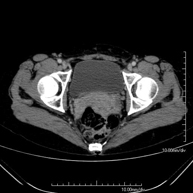

- Pelvis CT

Diagnostic test that involves obtaining high-definition anatomical two- and three-dimensional images of the pelvis (bone structures, vascular structures, bladder, uterus and ovaries, prostate and seminal vesicles, ureters, etc.) using CT (computed tomography) equipment. Most studies require the use of iodinated contrast.

- Pelvic bone CT

Radiological examination based on an X-ray system and detectors that rotate around the patient, reconstructing the images by computer (multidetector computed tomography - MDCT) to study the bones, muscles and joints of the pelvis.